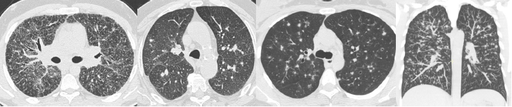

Micronodules

COCHE E. - 2021 - UCL

Cardio-thoracique DES SPECIALITE

Verre dépoli

GHAYE B. - 2021 - UCL